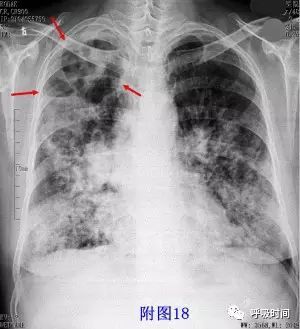

图 18 肺结核:右肺上叶多发空洞,内可见气液平;可见肺尖帽征